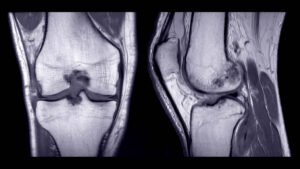

Knee arthrogram:

• Detects: Meniscal tears, ligament injuries (ACL, PCL, collaterals), cartilage lesions, post-surgical complications

• Less common (standard MRI often sufficient)

• Why it’s ordered: When standard MRI is inconclusive or post-surgical evaluation needed